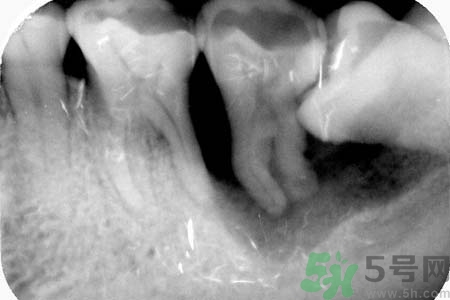

5、如果智齒經(jīng)常疼,而且疼的比較厲害,可能已經(jīng)引發(fā)牙冠周軟組織發(fā)炎,所以導(dǎo)致智齒腫脹、疼痛;再如果智齒長的位置很歪,影響其它牙齒正常咀嚼,也影響美觀,最好是考慮拔牙。拔牙前提是確保牙冠周圍沒有炎癥,才能安排拔牙,免除后顧之憂,拔智齒是拔牙里最難的一種,所以一定要到正規(guī)口腔醫(yī)院,請(qǐng)正規(guī)醫(yī)師進(jìn)行專業(yè)拔牙。

6、如果智齒經(jīng)常疼,而且疼的比較厲害,可能已經(jīng)引發(fā)牙冠周軟組織發(fā)炎,所以導(dǎo)致智齒腫脹、疼痛;再如果智齒長的位置很歪,影響其它牙齒正常咀嚼,也影響美觀,最好是考慮拔牙。拔牙前提是確保牙冠周圍沒有炎癥,才能安排拔牙,免除后顧之憂,拔智齒是拔牙里最難的一種,所以一定要到正規(guī)口腔醫(yī)院,請(qǐng)正規(guī)醫(yī)師進(jìn)行專業(yè)拔牙。